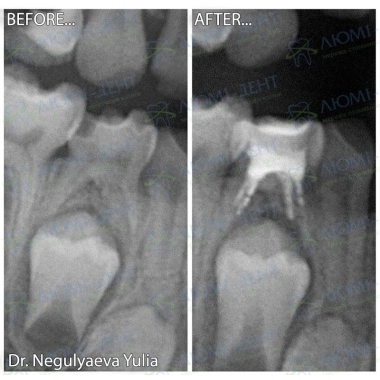

Примеры работ доктора Негуляевой Ю.А.